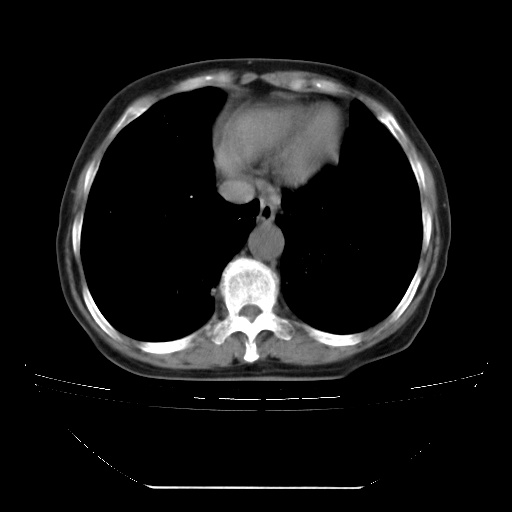

患者女性,72岁,慢性咳嗽3月余,曾抗炎治疗无效果,最近抗结核治疗约半月余,症状缓解。

ct示两肺粟粒状病灶,以两肺上叶尖后段及下叶背段分布为主;首先考虑结核。请战友们分析。

查原发灶吧,肺内转移瘤!肝内也有病灶,需强化明确。

两肺内病灶呈小结节状和树芽状,纵膈的肿大的淋巴结密度不均匀,并见有钙化,考虑为两肺结核可能更大些。

两肺内病灶呈小结节状和树芽状,纵膈的肿大的淋巴结密度不均匀,并见有钙化,多形态病灶,考虑为两肺结核,肝内考虑小囊肿。